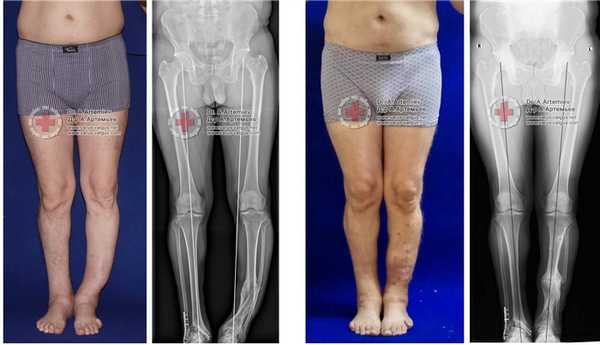

Пациентов фотографировали до, в процессе коррекции и после завершения лечения. При этом соблюдали определенные правила: ровный фон, камера на уровне коленных суставов, фокусное расстояние около 3 метров. Соблюдение этих правил позволяло получать качественные изображения с минимальными искажениями и производить сравнение внешнего вида ног на различных этапах коррекции. Особое внимание уделяли качеству выполнения фотографий до начала лечения у пациентов с идиопатической Х-образной формой ног, поскольку именно они представляли особое значение при обсуждении плана и прогноза коррекции (Рисунок 3).

Документирование, в первую очередь, выполнение фото и видео до операции, значительно облегчают оценку формы нижних конечностей на завершающих этапах коррекции с помощью аппарата Илизарова и позволяют получить желаемый результат, удовлетворяющий пациентов не только по клинико-рентгенологическим показателям, но и по внешнему виду.

Рисунок 3 - Фото до операции в свободной стойке (а, б) и в положении максимального сближения стоп (в, г), а также рентгенограмма нижних конечностей этой пациентки по всей длине в свободной стойке (д).